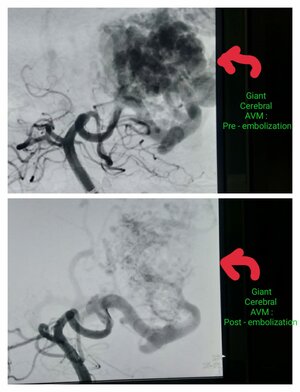

Pre procedure- Giant cerebral AVM Pre embolization & Post Embolization procedure- Giant Cerebral AVM Post embolisation.